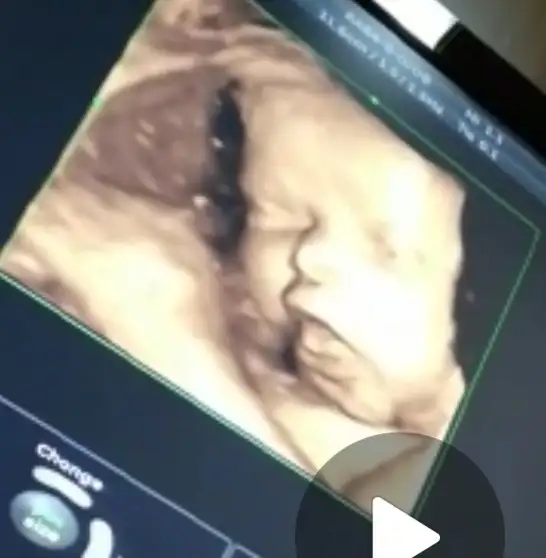

Oyy yerim ben onu yaa kızlar babacı olur zatenSlm kizlar hepinize tesekkur ederim bugun eve gectik detayli yazamamistim spinal sezeryan yapmistim bende basagrisi olmadi sutum hemen geldi bebegim cok sukur guzel emdi gogus pompasini getirmistim gerek olmadi hazir mamada getirdim onada gerek kalmadi yaa dogumda kizimi o an gorunce çookk agladim inanamadim suan karsimda uyuyor doyamiyorum buarada siz siz olun pijama takimi fazla koyun ben 1 gece kaldim benim kanamam cok olmadigi halde 2 pijama takimi kirlendi son gun gecelik giydim bu arada foto cekimimizde oldu kizim resmen babasiyla aşk yaşiyor simdiden papucum dama atildihimm birde kizim ayni babasi bana benzeyen tarafi çenesi oda ultrasondada belliydi benzedigi